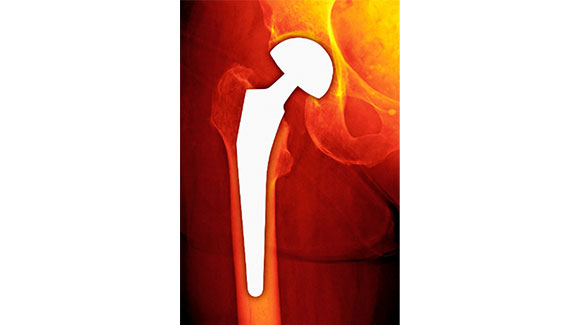

人工骨頭挿入術

人工骨頭挿入術は、高齢者に多い大腿骨頸部骨折の治療法で、骨癒合が期待できない折れ方をした大腿骨の骨頭を人工物に置き換えて連結する手術です。人工股関節置換術とは異なり、骨盤側のカップ設置は行いません。

手術は一般的に全身麻酔で行われ、股関節の侵入方法には前方・後方がありますが、後方アプローチが一般的です。手術時間は1時間弱です。

高齢者が対象のため、リハビリの進行には個人差があり、平均して歩行可能になるまで2週間以上、退院まで3週間以上かかることが多いです。